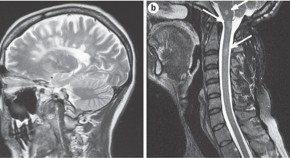

• Cavernous malformations (CMs) are vascular malformations that mainly occur in the brain. Many patients with such lesions are asymptomatic; however, individuals with CMs can present with seizures, focal neurological deficits or intracranial hemorrhage. In this Review, Batra and colleagues examine the pathology, natural history and imaging of CMs. Furthermore, the authors discuss the use of pharmacology, surgical resection and stereotactic radiosurgery in the management of such lesions.